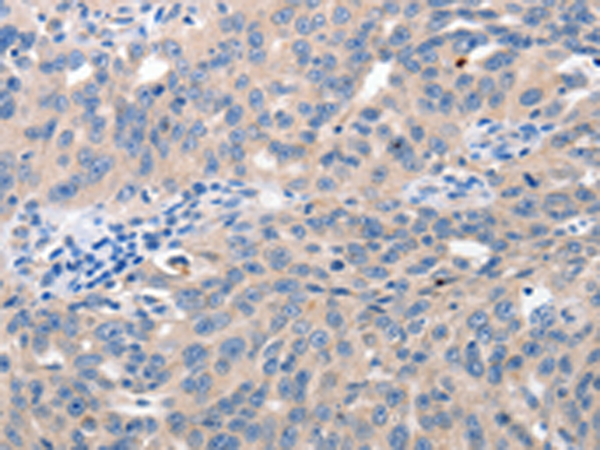

分类: 科研抗体货号: P07389别名: MUM1; LSIRF; SHEP8; NF-EM5应用: IHC反应种属: Human, Mouse